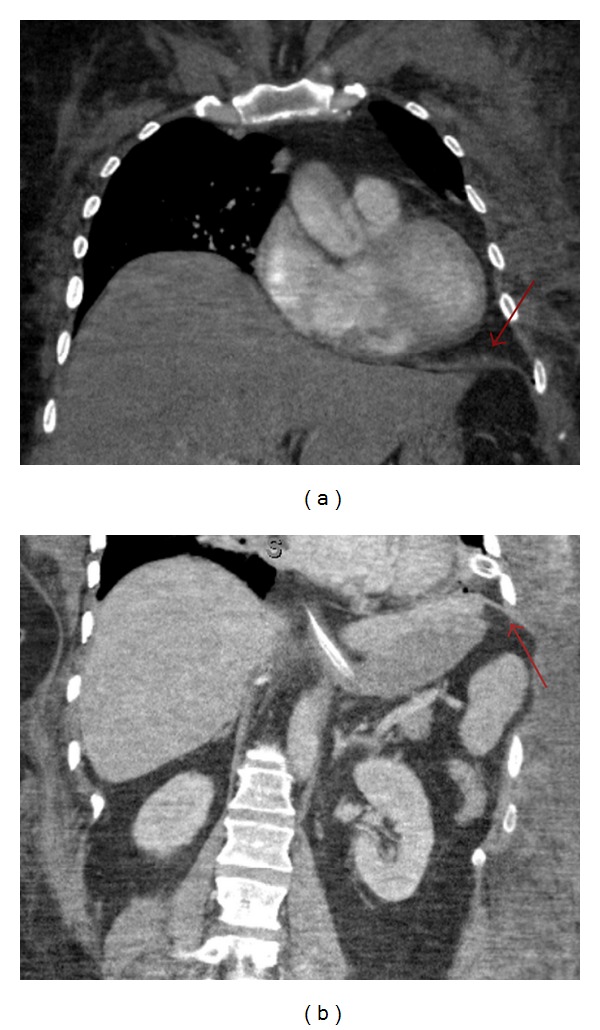

Figure 4.

Coronal CT images of the chest and abdomen taken 1 week after surgical repair of the diaphragm (red arrow) show no residual transdiaphragmatic or intercostal herniation.